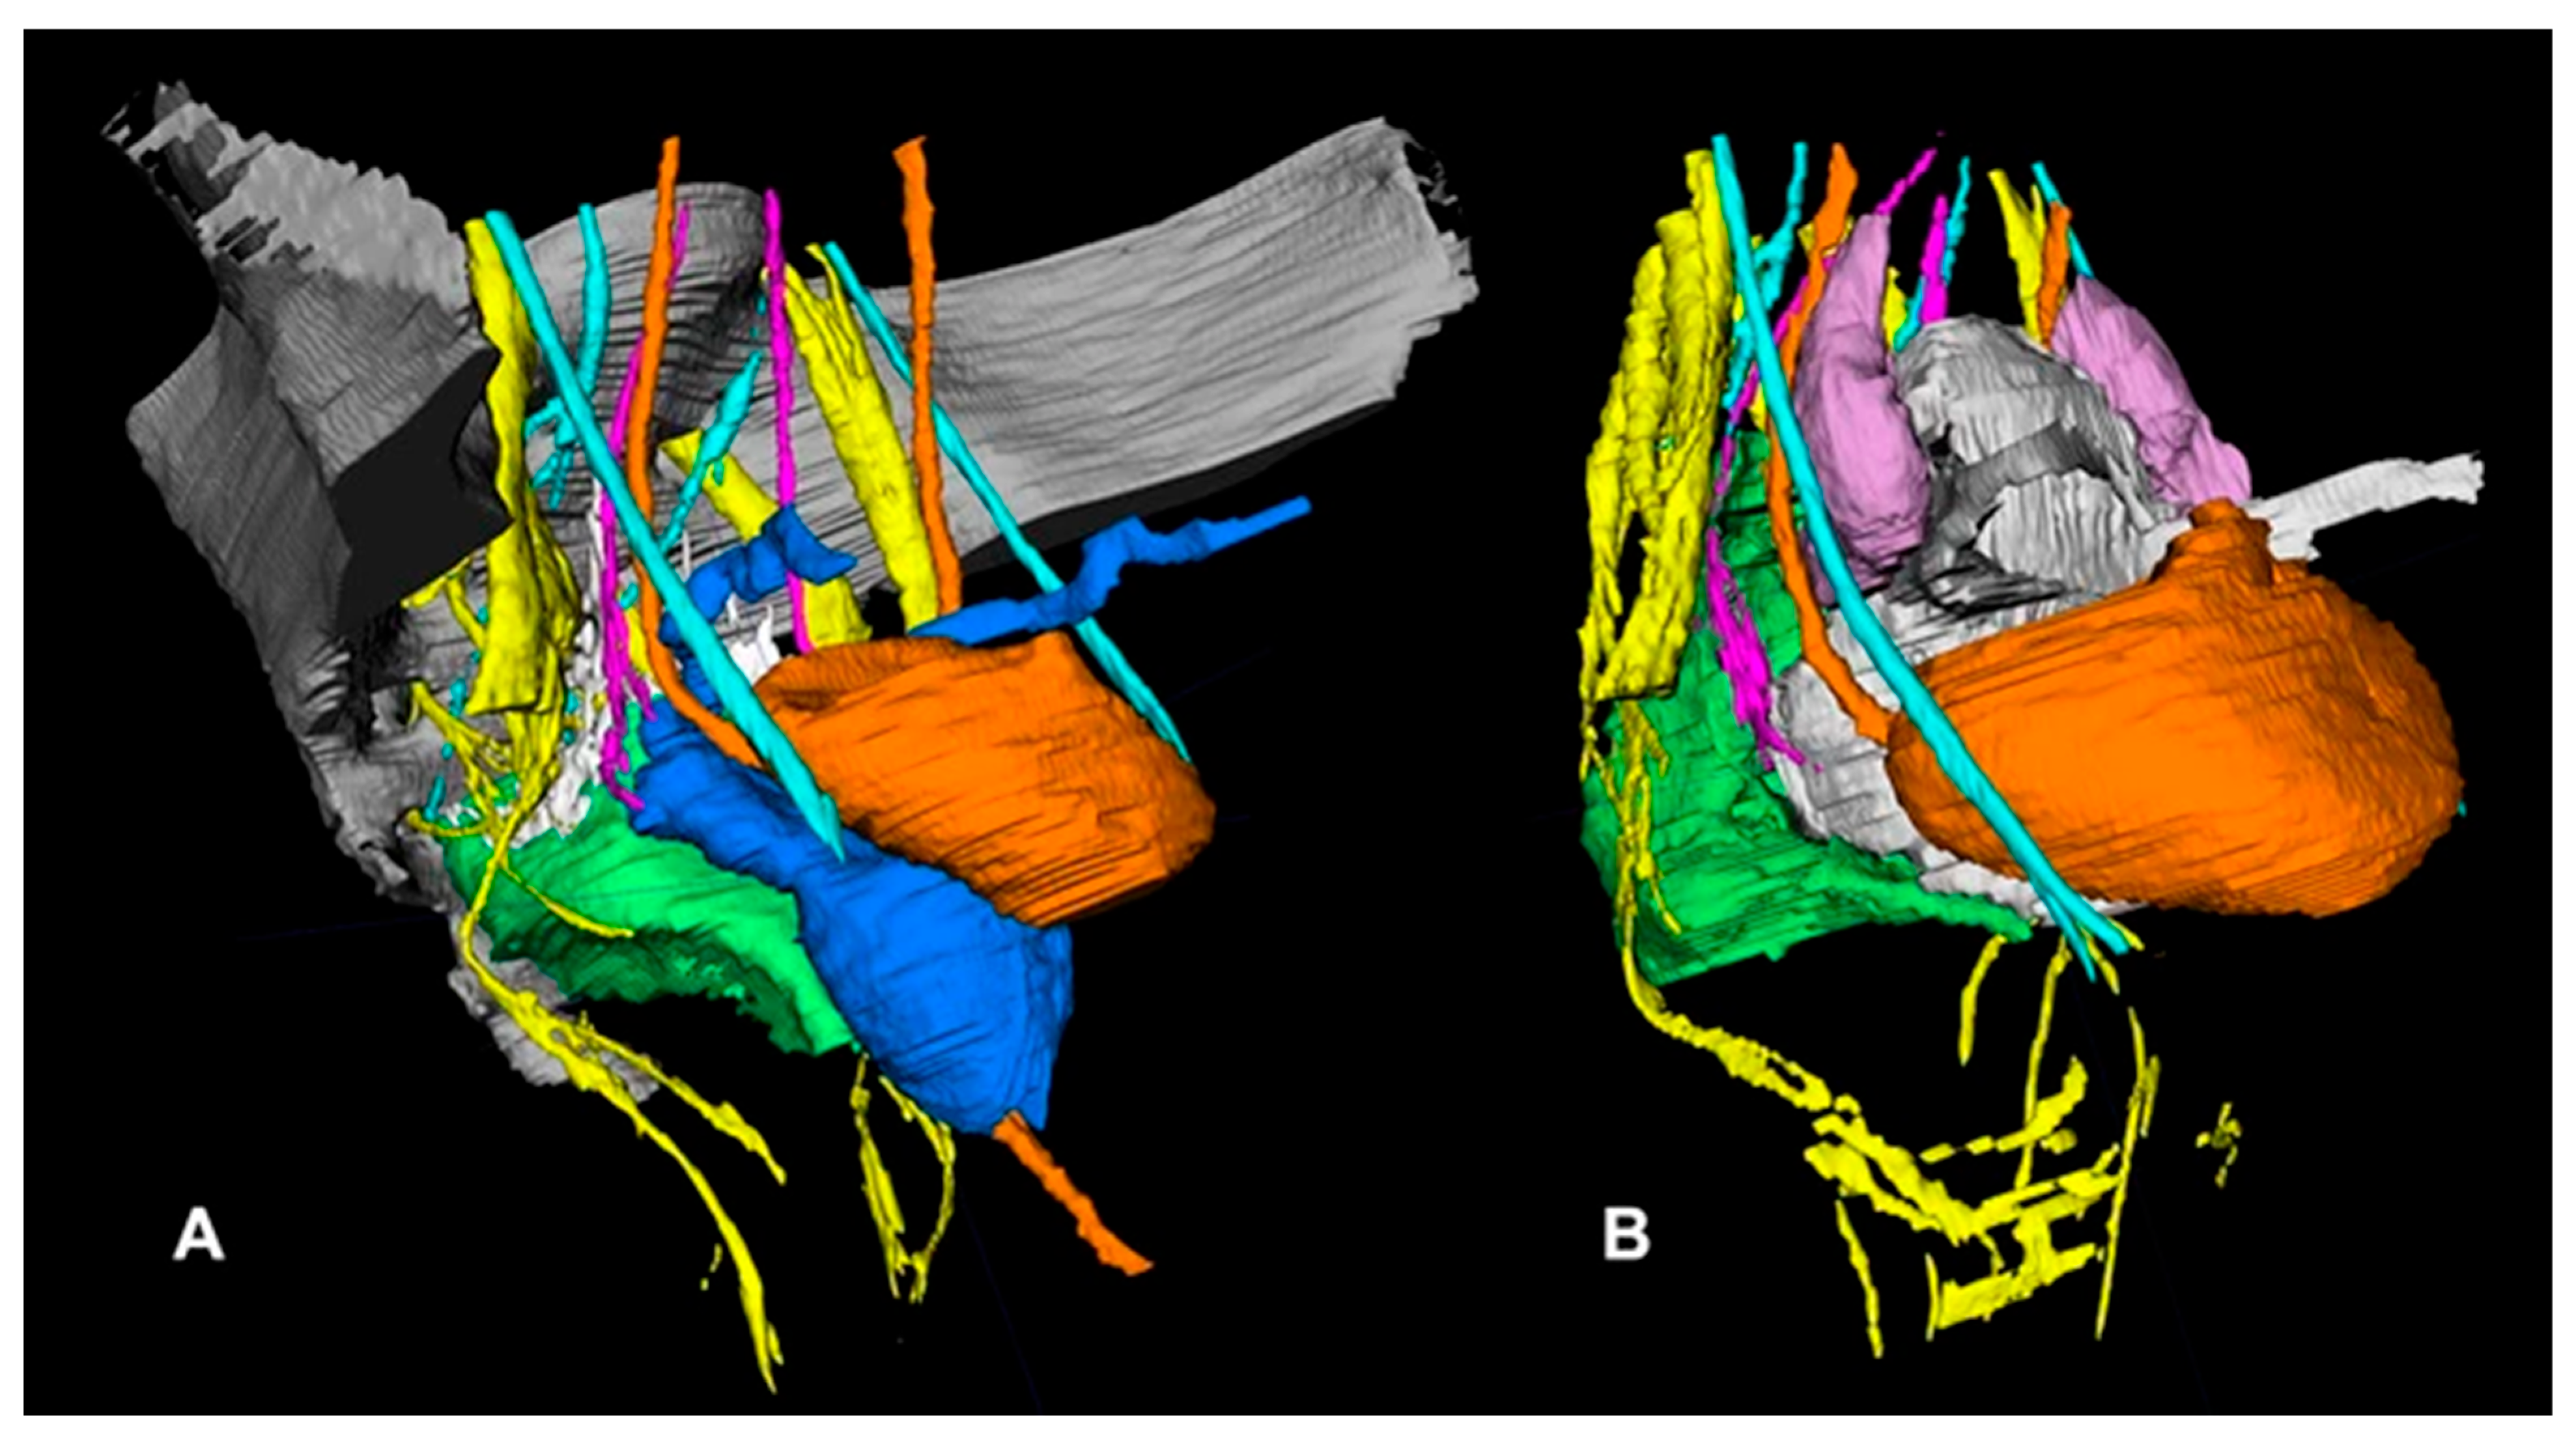

- Wijsmuller, A.R.; Giraudeau, C.; Leroy, J.; Kleinrensink, G.J.; Rociu, E.; Romagnolo, L.G.; Melani, A.G.F.; Agnus, V.; Diana, M.; Soler, L.; et al. A step towards stereotactic navigation during pelvic surgery: 3D nerve topography. Surg. Endosc. 2018, 32, 3582–3591. [Google Scholar] [CrossRef] [PubMed]

- Muller, C.O.; Mille, E.; Virzi, A.; Marret, J.-B.; Peyrot, Q.; Delmonte, A.; Berteloot, L.; Gori, P.; Blanc, T.; Grevent, D.; et al. Integrating tractography in pelvic surgery: A proof of concept. J. Pediatr. Surg. Case Rep. 2019, 48, 101268. [Google Scholar] [CrossRef]